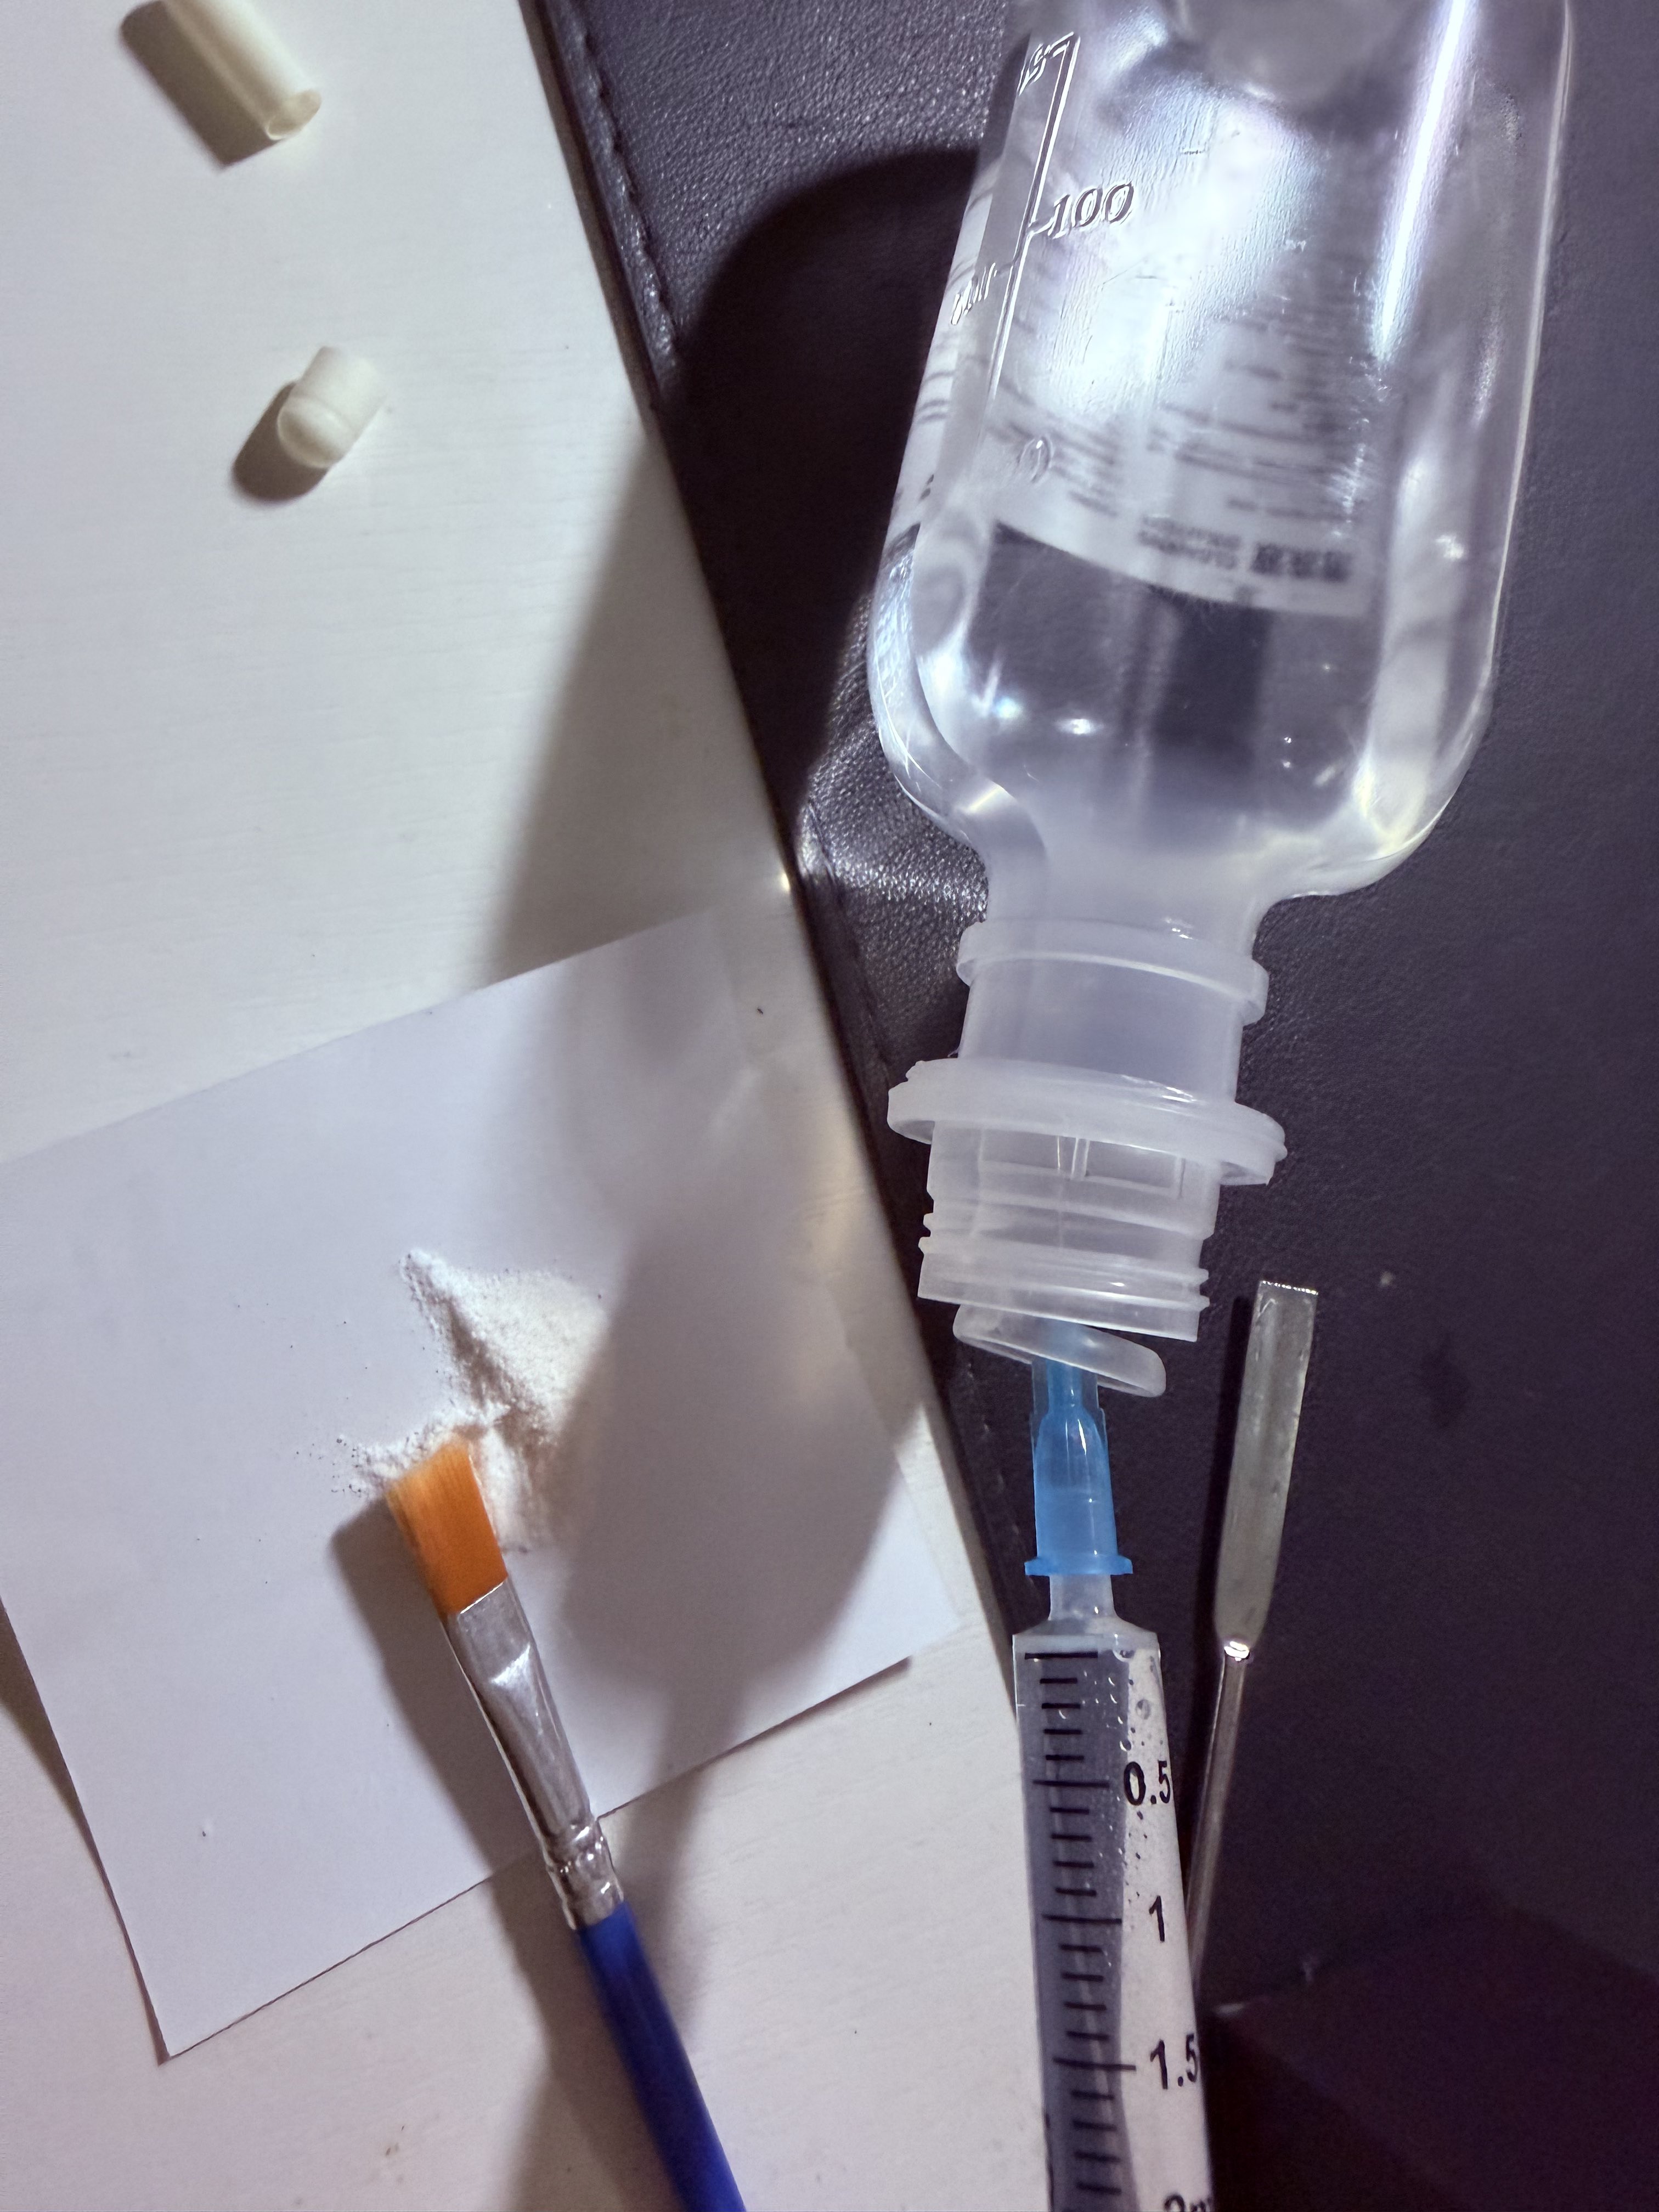

对于药物过量引起的中枢神经系统副作用,有一些不常见或常见的药物来控制症状。

炽烈已极 @AnIncandescence纳洛酮:可用于阿片类药物过量(可获取的上市药品)需舌下给药,因肝脏首过代谢口服时利用度很低;效果持续30-90min;亦可用于酒精中毒的促醒等,但谨慎使用。